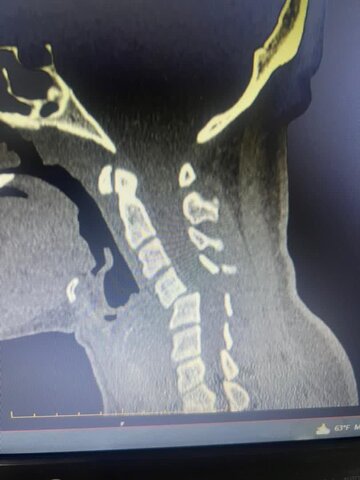

، عمل جراحی ستون فقرات مهسا تجری ورزشکار رشته شنا که در حین تمرین دچار حادثه شده بود با موفقیت انجام شد.

به گزارش روابط عمومی هیات پزشکی ورزشی استان گلستان،دکتر آیت اللهی رئیس هیات پزشکی ورزشی گلستان ضمن اعلام این خبر گفت: عمل جراحی توسط دکتر امید مومن فوق تخصص جراحی ستون فقرات و از همکاران هیات پزشکی ورزشی و عضو هیات علمی دانشگاه علوم پزشکی گلستان انجام شد. وی اظهار امیدواری کرد که این قهرمان گلستانی هر چه زودتر به عرصه ورزش قهرمانی بازگردد.